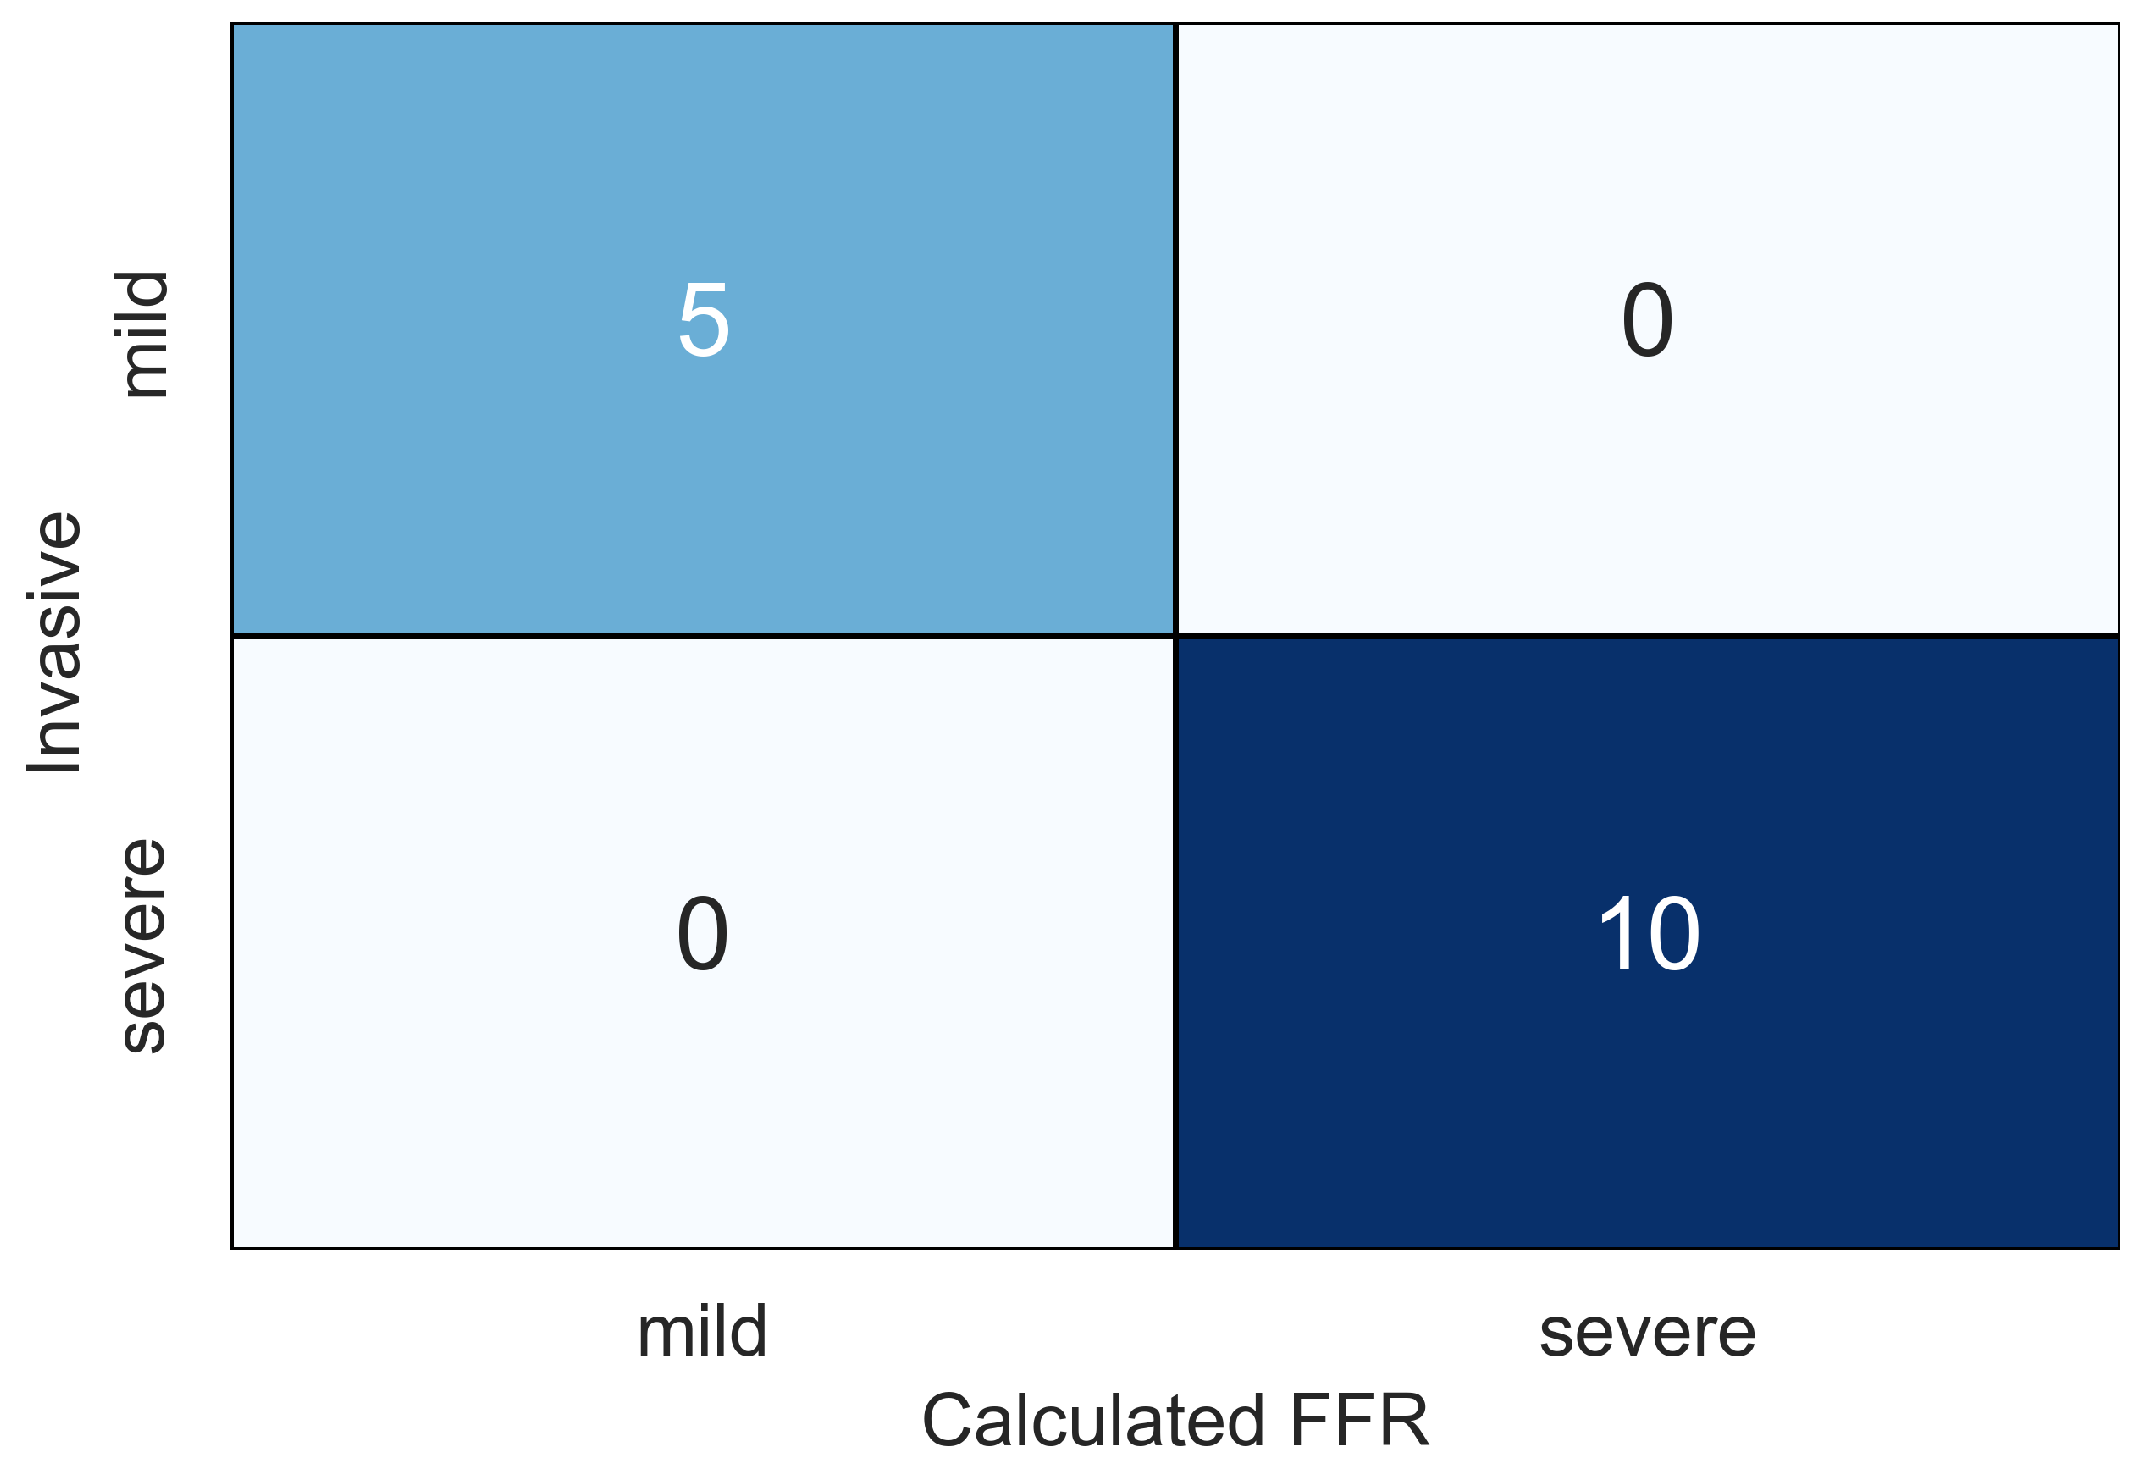

4. Results

5. Discussion